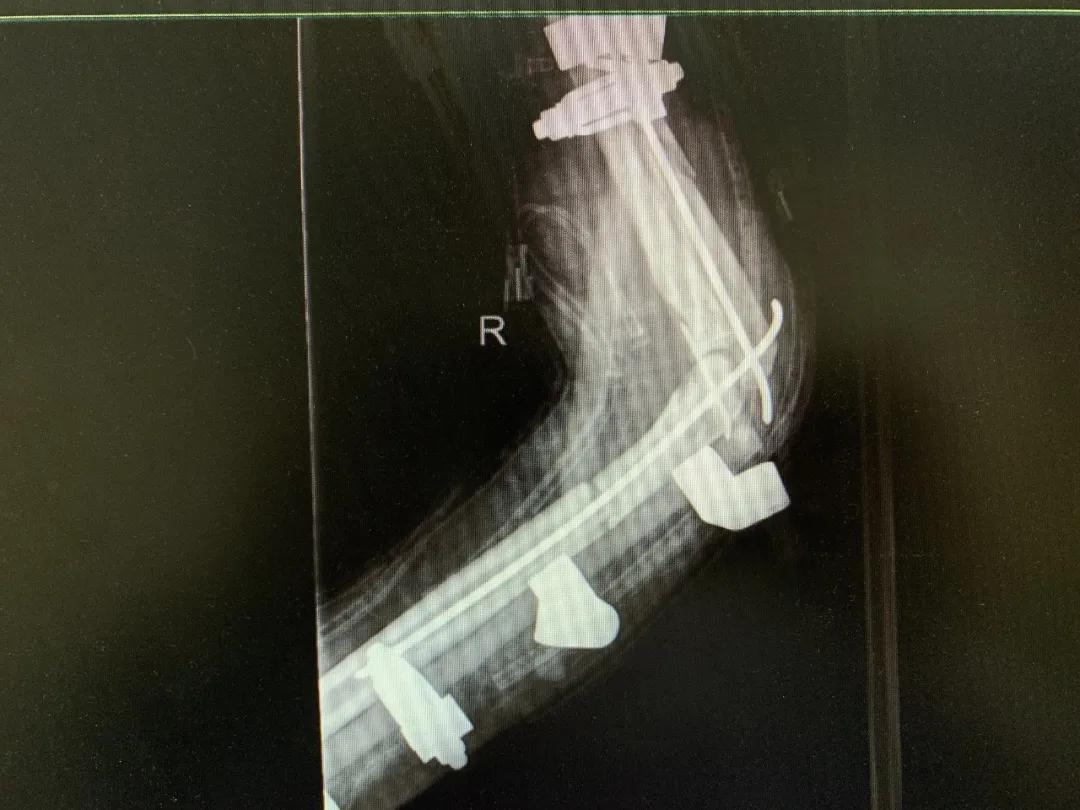

“正常的肢体都有皮肤保护着,如果没有皮肤,我们的肌肉、血管、神经、骨骼露在外面,都会发生坏死。”苑芳昌介绍,伤者的情况非常复杂,伴有多发骨折、肱骨骨折、骨关节的多发错位,还有腕部的骨折,更有血管、神经损伤。不仅如此,伤者右臂在机器里面受到绞伤,肌肉也已经大面积挫伤,各种复杂情形交织在一起甚至让手术“无从下手”。

清创、止血、接骨、将粉碎的骨块一块块拼接完整,同时给予VSD敷料负压引流。经过三次清创清除后,明确了坏死的皮肤等组织,创面好转,肉芽组织良好……